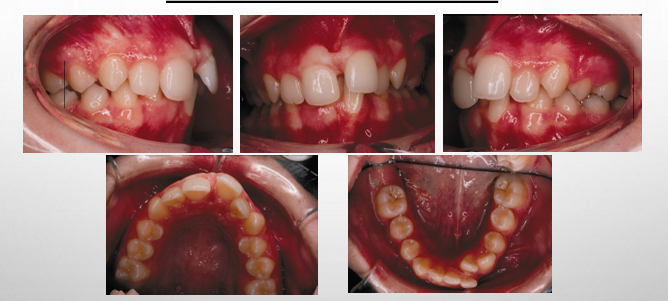

standard orthodontic composite

-facial: profile view, frontal (full face) at rest, frontal (full face) with natural smile

-dental: upper occlusal, lower occlusal, right buccal in occlusion, front occlusion, left buccal in occlusion

dental (model) analysis

-4 categories to assign dental analysis findings:

1) sagittal (A/P)

2) vertical

3) transverse

4) alignment

intraoral exam- sagittal

-use the buccal photos and diagnostic models

intraoral exam- transverse

-transverse plane- use the frontal and buccal photos

-posterior crossbites

-midline analysis: coincidence with each other, coincidence with face

midline assessments

1) maxillary midline to facial midline

2) intermaxillary midline

3) mandibular midline to facial midline

intraoral exam- alignment

-crowding

-spacing

-rotations

-diastemas